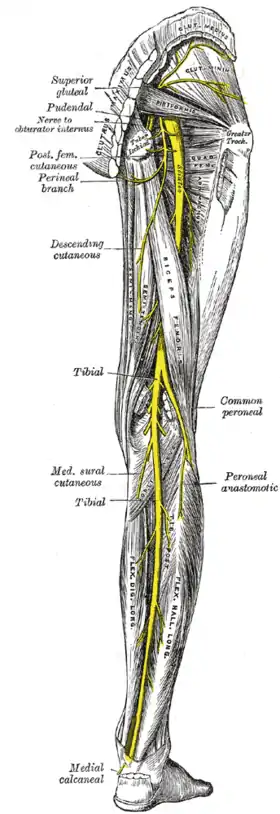

The arteries of the gluteal and posterior femoral regions. Nerves of the right lower extremity Posterior view.

Nerves of the right lower extremity Posterior view.